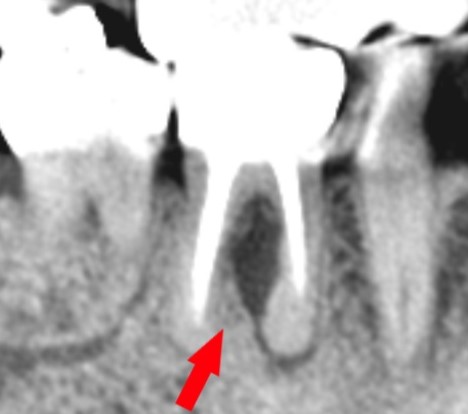

短い根管充填のデンタルレントゲン写真

根管充填が短く、やり直しが必要です。

レントゲン写真(CT像)ですぐ分かります。

デンタルレントゲン上で見える根管充填の不足部分

根管充填が短い部分は、上の赤い部分です。

赤矢印は、化膿で骨が溶けている部分です。